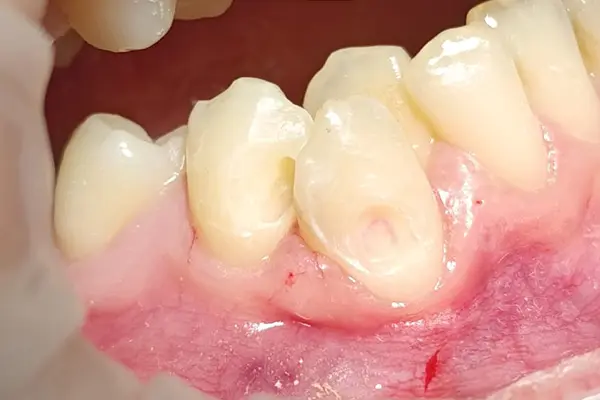

В этом клиническом случаем от Виталия Семёновича Лаврысь мы рассмотрим лечение кариеса дентина 43 и 44 зуба с использованием композитов B&E.

Пломбировались кариозные поражения с помощью материалов B&E flow (адаптивный слой) и Xs-Fil линейной техникой.

После заполнения использовалась полировка дисками ТОР. Композит хорошо пакуется брашем и адаптируется с помощью кисточки и смолы.

Для достижения наилучших результатов Виталий Лаврысь рекомендует делать скос не менее 2.0 мм и провести полировку.

Обратите внимание, что материал «схамелеонил»! Эффект «хамелеона» достигается при правильной «игре» с оттенками дентинных и «боди» по толщине. По консистенции и оптическим свойствам материалы B&E ближе к композитам Gradia Direct (GC, Япония). Это показывает, что при правильном подходе можно добиться очень естественного и эстетичного результата, который меняется в зависимости от освещения и угла зрения.